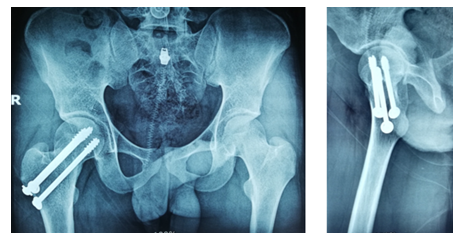

After selecting a case according to inclusion and exclusion criteria, patients were evaluated preoperatively. An elaborate history was taken. This was followed by a general examination and local examination. After admission, patients were put on surface traction to the affected limb with 1/10th of the patient's body weight. All patients underwent preoperative counselling regarding the operative procedure, probable complications, outcome, and other treatment options, along with their merits and demerits. After being informed, written consent was obtained. After preparing the patients for operation, Closed reduction is performed with the patient in the supine position on a fracture table (Figure 1). Reduction was confirmed by C-arm. After reduction, three guide wires are placed, usually in an inverted triangular fashion (Figure 2).

The screw lengths are measured, and drilling is performed using a 4.5 mm cannulated reamer. The screws are then inserted (for the BDSF technique, a specific sequence of middle, then superior, and lastly inferior screw insertion is to be followed). All three screws are inserted less than 5 mm subchondrally (Figure 3,4). In all cases, a prophylactic antibiotic was given. In the postoperative ward, proper fluid and hemodynamic balance were ensured. Change of posture was done twice an hour. The antibiotic was continued for 3 days. Analgesics were given to ensure a pain-free postoperative period. On the first postoperative day, patients were allowed to sit on the side of the bed. Patients were being educated about breathing exercises, isometric quadriceps exercises, gluteal exercises, and ankle pumping exercises. An immediate postoperative X-ray was done (Figure 5). After checking the dressing, on 4th POD, they were discharged from the hospital if their postoperative period was uneventful. Oral antibiotics were given for 10 days. Advice was given to continue isometric quadriceps exercise. Regarding ambulation, they were advised to do non-weight-bearing (of the affected side) crutch ambulation until directed by the physician. Use of elevated toilet seats onwards is also advised. The next follow-up would be given at the 14th POD. The first follow-up was given at 14th POD to check any signs of infection, pain status, and distal neurovascular status. The stitch was removed on the same day. Advice given about isometric quadriceps exercise, active abduction, extension exercise, and stretching exercise of the hip joint. The next follow-up was the 6th week after the operation. The range of motion was tested. An X-ray was done to check callus formation. Improvements were noted. Partial weight bearing was given at this follow-up. Subsequent follow-up was given at 12 weeks and every 4 weeks until union has been achieved or at least 9 months (Figures 6-10).